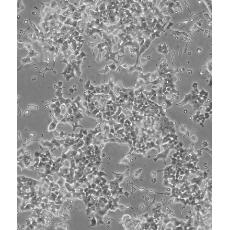

Beta-TC-6

產(chǎn)品名稱 Beta-TC-6

中文名稱 小鼠胰島素瘤胰島β細胞

組織來源 胰島素瘤

細胞種屬 mus musculus, mouse

生長特性 adherent

形態(tài)特征 epithelial

細胞描述 這株細胞來源于轉(zhuǎn)基因小鼠中生長的一個胰腫瘤(胰島素瘤)。這種小鼠攜帶了大鼠胰島素II基因啟動子調(diào)控的SV40早期基因的假基因結(jié)構(gòu)。細胞包含豐富的胰島素和小量的胰高血糖素及生長抑素。響應(yīng)葡萄糖而分泌胰島素